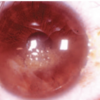

IMAGENES SIGNOS QUERATOCONO

Signo de RIzzuti

enfoque de la luz dentro del limbo nasal cuando se ilumina con una linterna desde el lado temporal

Signo de Munson(SIGNO QUERATOCONO)

desviación inferior del contorno del párpado inferior en la infraversión

Anillo de Fleischer(SIGNO QUERATOCONO)

Anillo café encontrado en la base del cono formado por disposición de hierro en el epitelio basal, que se vuelve más estrecho y bien definido con la progresión de la enfermedad

Estrías de Vogt

líneas finas y paralelas observadas en el estroma posterior en el ápice del cono, que desaparecen con la aplicación de presión externa